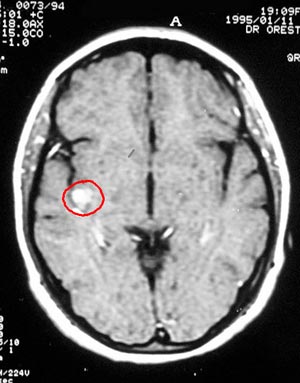

4a) Astrocitoma pilocítico

Figura 61 - Ressonância nuclear magnética pré-operatória.